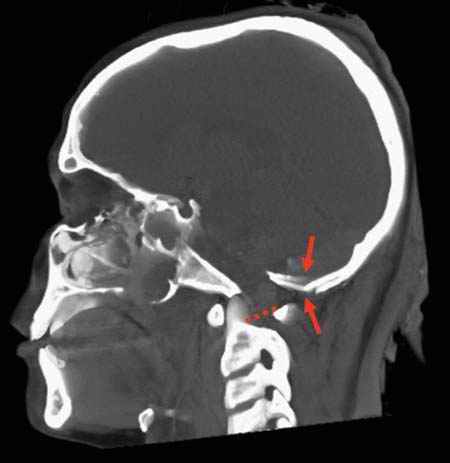

As is well known from clinical medicine, mid-face fractures can also extend over the maxilla and the zygomatic bone (Figure D3.2.8). These fractures arise from a direct impact to the face. Depending on the involved structures, these fractures are classified as Le Fort I-III. This classification can be difficult, especially in cases of vehicle accidents, where, due to the massive damage, multiple fractures are often seen. In such cases, the Le Fort classes overlap (Figure D3.2.9). Mandibular fractures occur due to punches, falls, and vehicle accidents, to name just a few mechanisms. Direct fractures are seen paramedially, whereas indirect fractures are mostly located in the region of the joint and the mandibular body.

Postmortem imaging can display such possibly telltale injuries in a rapid and nondestructive manner, thus sparing the face from further disfigurement or the pathologist from missing a potentially important finding.